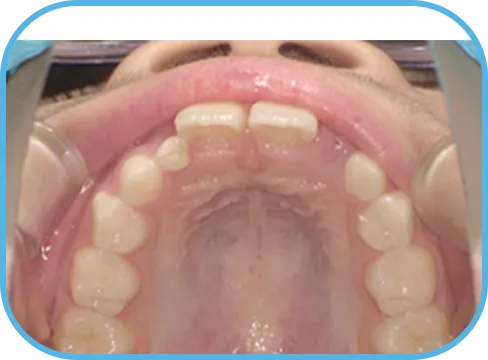

• 上 顎

治療前上顎からの歯の様子

治療後上顎からの歯の様子

主 訴

上の前歯がねじれている、ガタガタ

治療内容

インビザライン・ファースト

治療期間

8か月

治療費(税別)

450,000円+診断料50,000円

リスク・副作用

• 親知らずの影響や加齢などによって、凸凹が生じる可能性があります。

• 治療の初期段階では痛みや不快感が生じやすくなりますが、1週間前後で慣れます。

• 顎の成長発育によって、噛み合わせや歯並びが変化する可能性があります。

• 状況により当初予定した治療計画を変更する可能性があります。